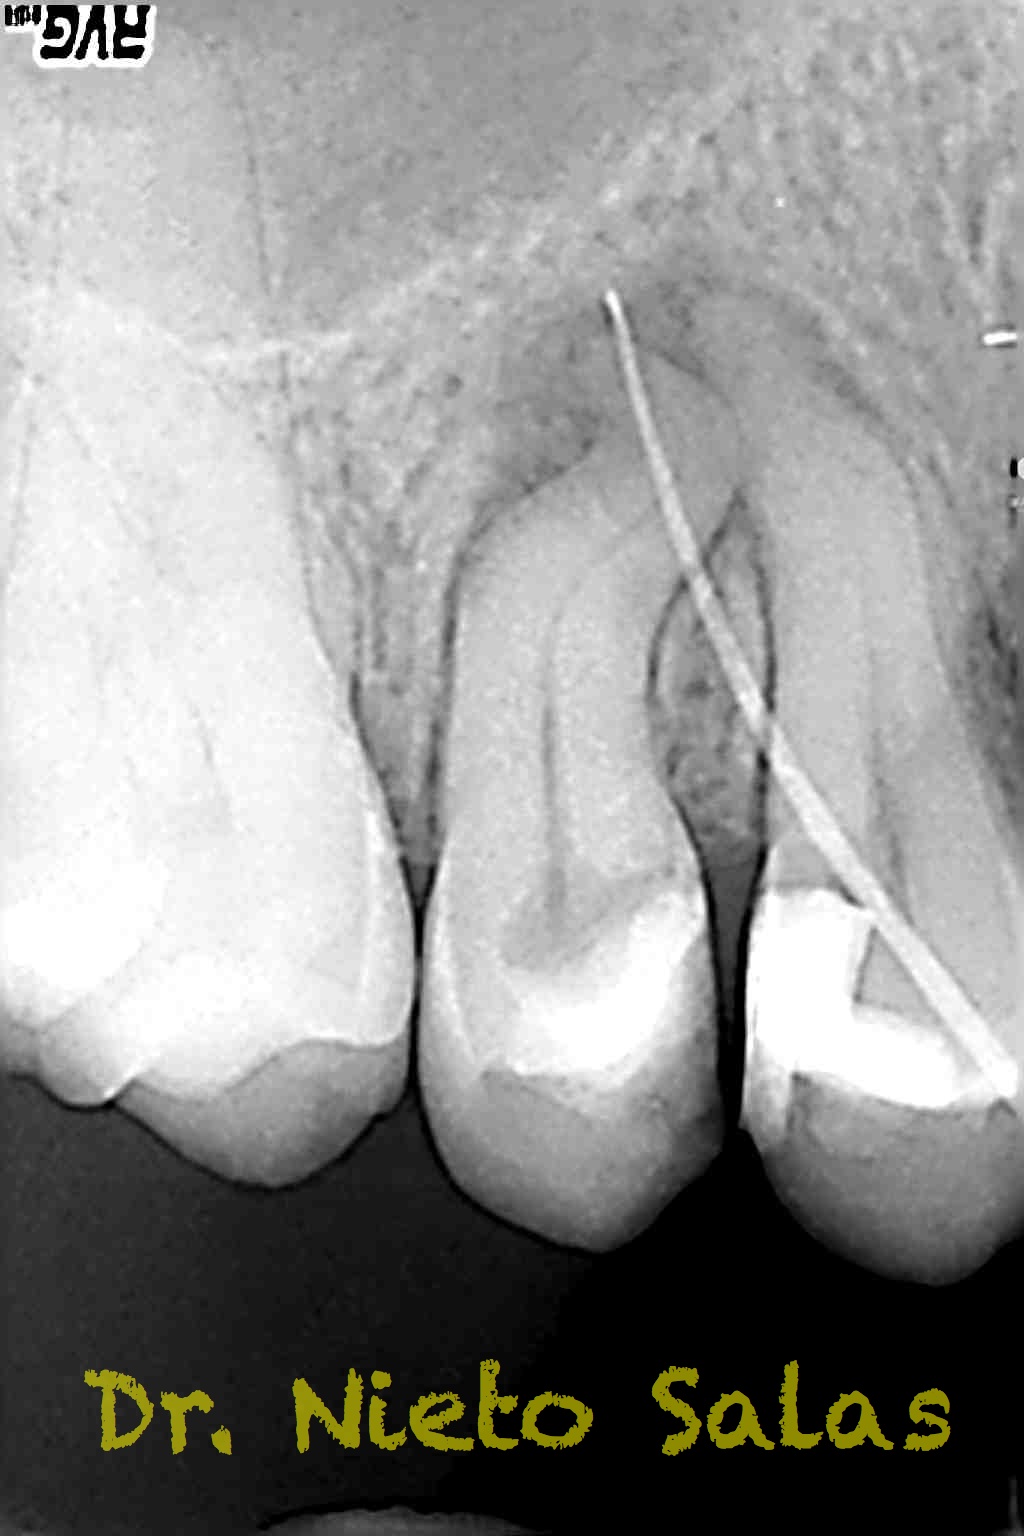

Se nos presenta en la clínica un par de casos de características similares, con lo cual las hemos tratado igual:

Ante estas situaciones, lo que no debemos es intentar llegar a la zona apical rápido, primero prepararemos el tercio medio-coronal, pero sin perder la permeabilidad del conducto con limas de muy pequeños diámetro.

Una vez que tenemos la Long de trabajo, no debemos perderla, se recomienda mucha irrigación e intentaremos que nuestras limas trabajen en una superficie lo menor posible.

Con respecto a lo puramente endodóntico, la verdad que fueron unos casos de verdadero estrés para no perder la permeabilidad ni la long de trabajo, con técnica corona-apice y con un diametro apical de 20, instrumentado solo la parte apical con limas de Mtwo , la parte coronal me ayudé de ultrasonidos. No sé, que más contarte con respecto a la conformación de los conductos.